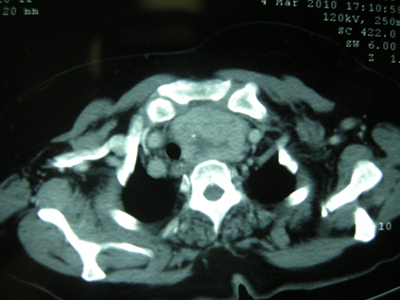

Tanıda öncelikle substernal guatr olasılığından şüphelenmek önemlidir. Boyunda guatr tespit edilen hastalarda muayenede palpasyon çok önemlidir. Palpasyonda yutkunma esnasında ve boyun ekstansiyonunda guatr alt sınırı palpe edilemiyorsa ve sternoklaviküler bölgede kitle devamlılık gösteriyorsa substernal guatrdan şüphelenilmelidir. Tanıda valsalva manevrası kullanılabilir.[22] Ancak büyük substernal guatrların %20'sinden fazlasının boyundan palpe edilemeyebileceği unutulmamalıdır.[14] Substernal guatrdan şüphelenilen olgularda direk radyografide üst mediastende radyoopasite ve trakeal itilme görülebilir (Resim 1). Hastaların yaklaşık %61'inde direk grafide trakeada itilme mevcuttur.[13] İçerisinde kalsifikasyon olan guatrlarda mediastende kalsifiye lezyon izlenebilir. Ultrasonografi boyundaki kısımla ilgili bilgi verebilir ancak substernal uzanımı göstermede yetersiz kalır. Sintigrafik incelemeler bazı tiroid lezyonları radyoaktif iyodu tutamadıklarından az oranda fayda sağlar. Bu sebeple ender olarak kullanılmaktadır.[14] Bilgisayarlı tomografi, guatrın uzanımını ve komşu yapılara yakınlığını çok iyi gösterdiği için tanıda altın standarttır (Resim 2). Damarsal yapılara yakınlığı göstermek için kontrastlı tomografi tercih edilebilir. Tiroid hacmini belirlemek amacıyla üç boyut rekonstrüksiyonlu spiral tomografi yapılabilir.[23] Manyetik rezonans görüntüleme komşu yumuşak dokularla olan ilişkiyi göstermede yardımcı olabilir. İnce iğne aspirasyon biyopsisi yapılabilir ancak mediastene uzanan bölümden alınması zordur. Bu sebeple mediastene uzanan kısımdan aspirasyon biyopsisi önerilmemektedir.[14] Substernal guatrlarda malignite riski literatürde %6 ile 21 arasında değişmektedir.[13] Mathew ve ark. 2008 yılında yaptıkları metaanalizde de benzer oranlar bulmuş ancak incelediği bir grup çalışmada boyundaki guatrlara göre daha yüksek malignite riski olmadığını vurgulamıştır.[2] Ailede tiroid hastalığı öyküsü, boyuna radyoterapi uygulanması veya radyasyona maruz kalma, tekrarlayan guatr ve boyunda lenfadenopati varlığı malignite olasılığını artıran faktörlerdir.[2]

Resim 2: Aksiyal kesit bilgisayarlı tomografide trakeada itilmeye neden olan substernal guatr |